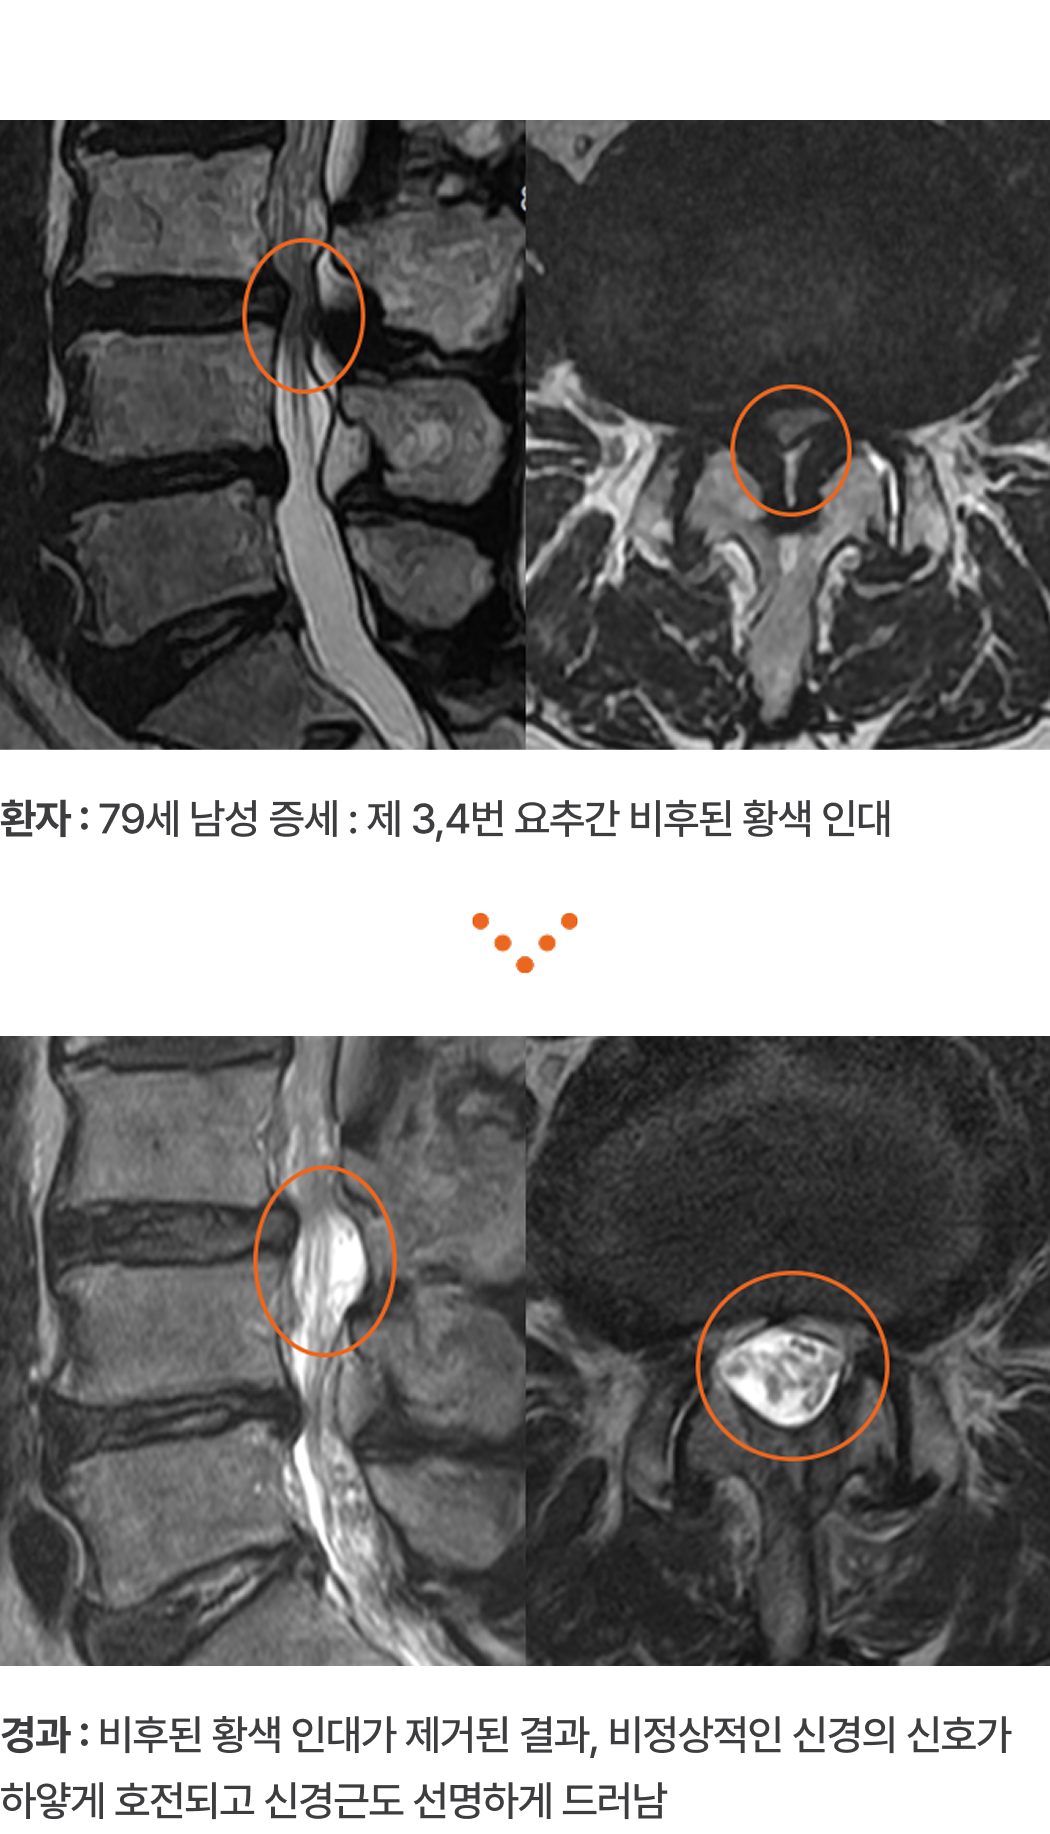

환자 :

79세 남성 증세 : 제 3,4번 요추간 비후된 황색 인대

경과 :

비후된 황색 인대가 제거된 결과, 비정상적인 신경의 신호가 하얗게

호전되고 신경근도 선명하게 드러남